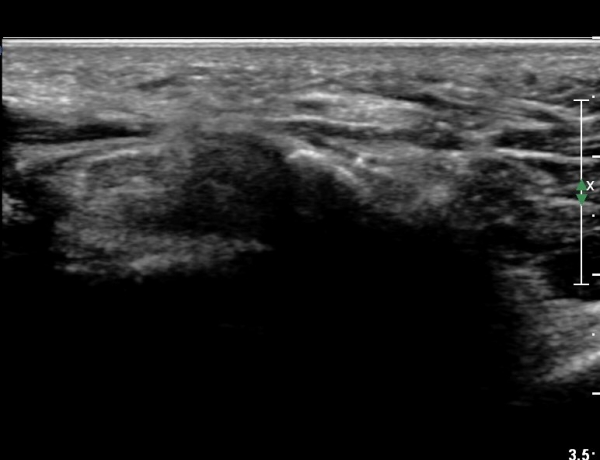

4 sono.jpg

¼Õ¹Ù´Ú ºÎÀ§¿¡¼­ ô°ñ½Å°æ ½ÉºÎ °¡Áö º´Áõ

(periphral neuropathy  of  deep palmar branch of ulnar nerve at palm level).